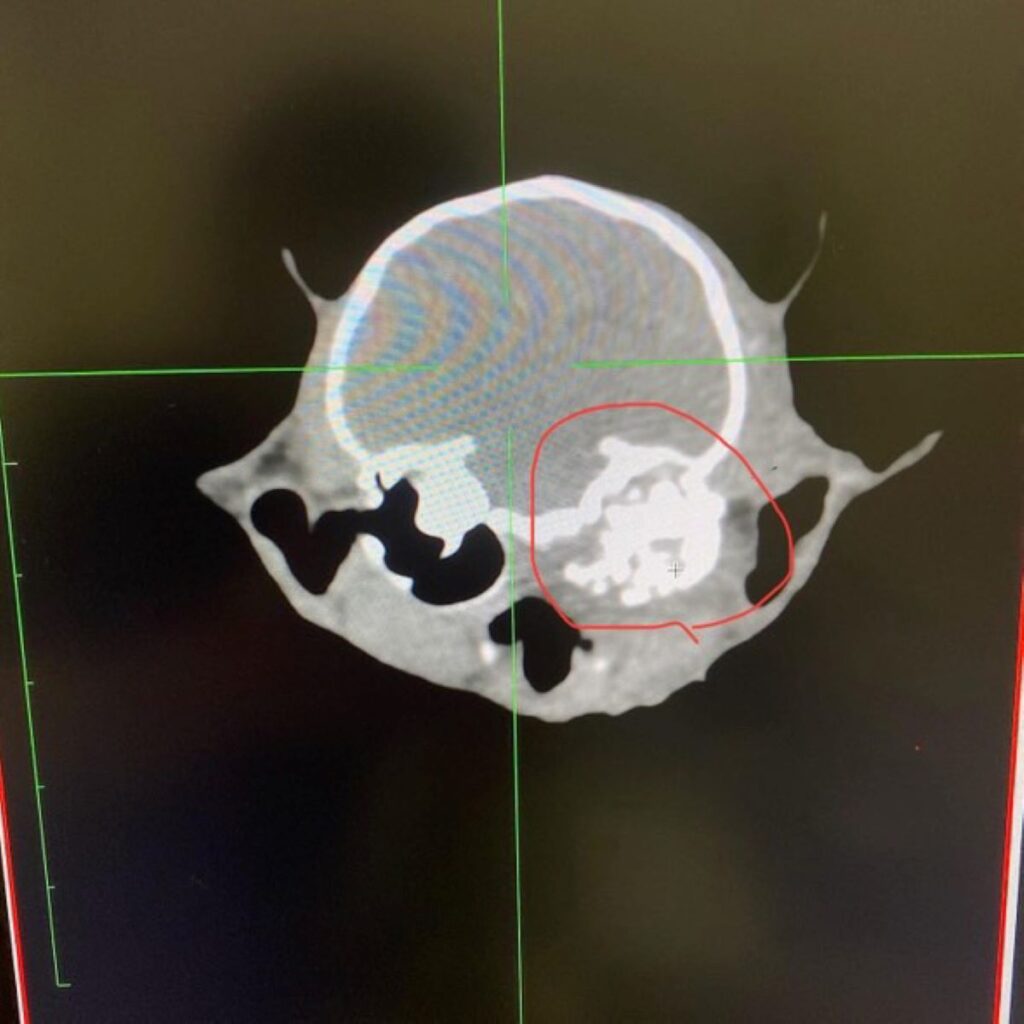

頭部CT(@satomi.iwamonさんより提供)